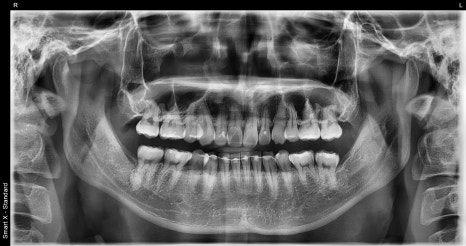

왼쪽 사진: 교정치료를 마친 지 약 10년이 지난 상태로, 전체 치열과 유지장치가 부착된 위치를 확인할 수 있는 엑스레이 사진입니다.